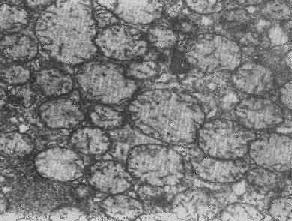

图1-8 心肌细胞线粒体

四、线粒体线粒体(mitochondrion)是细胞内主要的能量形成所在,故不论在生理上或病理上都具有十分重要的意义。 线粒体为线状、长杆状、卵圆形或圆形小体,外被双层界膜。外界膜平滑,内界膜则折成长短不等的嵴并附有基粒。内外界膜之间为线粒体的外室,与嵴内隙相连,内界膜内侧为内室(基质室)(图1-8)。在合成甾类激素的内分泌细胞(如肾上腺皮质细胞、卵甾滤泡细胞、睾丸的Leydig细胞等),线粒体嵴呈小管状。内外界膜的通透性不同,外界膜的通透性高,可容许多种物质通过,而内界膜则构成明显的通透屏障,使一些物质如蔗糖和NADH全然不能通过,而其他物质如Na+ 和Ca 2+等也只有借助于主动运输才能通过。线粒体的基质含有电子致密的无结构颗粒(基质颗粒),与二价阳离子如Ca2+及Mg2+具有高度亲和力。基质中进行着β氧化、氧化脱羧、枸橼酸循环以及尿素循环等过程。在线粒体的外界膜内含有单胺氧化酶以及糖和脂质代谢的各种转移酶;在内界膜上则为呼吸链和氧化磷酸化的酶类。 线粒体是对各种损伤最为敏感的细胞器之一。在细胞损伤时最常见的病理改变可概括为线粒体数量、大小和结构的改变: 1.数量的改变 线粒体的平均寿命约为10天。衰亡的线粒体可通过保留的线粒体直接分裂为二予以补充。在病理状态下,线粒体的增生实际上是对慢性非特异性细胞损伤的适应性反应或细胞功能升高的表现。例如心瓣膜病时的心肌线粒体、周围血液循环障碍伴间歇性跛行时的骨骼肌线粒体的呈增生现象。 线粒体数量减少则见于急性细胞损伤时线粒体崩解或自溶的情况下,持续约15分钟。慢性损伤时由于线粒体逐渐增生,故一般不见线粒体减少(甚至反而增多)。此外,线粒体的减少也是细胞未成熟和(或)去分化的表现。 2.大小改变 细胞损伤时最常见的改变为线粒体肿大。根据线粒体的受累部位可分为基质型肿胀和嵴型肿胀二种类型,而以前者为常见。基质型肿胀时线粒体变大变圆,基质变浅、嵴变短变少甚至消失(图1-9)。在极度肿胀时,线粒体可转化为小空泡状结构(图1-10,图1-11)。此型肿胀为细胞水肿的部分改变。光学显微镜下所谓的浊肿细胞中所见的细颗粒即肿大的线粒体。嵴型肿较少见,此时的肿胀局限于嵴内隙,使扁平的嵴变成烧瓶状乃至空泡状,而基质则更显得致密。嵴型肿胀一般为可复性,但当膜的损伤加重时,可经过混合型而过渡为基质型。 线粒体为对损伤极为敏感的细胞器,其肿胀可由多种损伤因子引起,其中最常见的为缺氧;此外,微生物毒素、各种毒物、射线以及渗透压改变等亦可引起。但轻度肿大有时可能为其功能升高的表现,较明显的肿胀则恒为细胞受损的表现。但只要损伤不过重、损伤因子的作用不过长,肿胀仍可恢复。 线粒体的增大有时是器官功能负荷增加引起的适应性肥大,此时线粒体的数量也常增多,例如见于器官肥大时。反之,器官萎缩时,线粒体则缩小、变少。